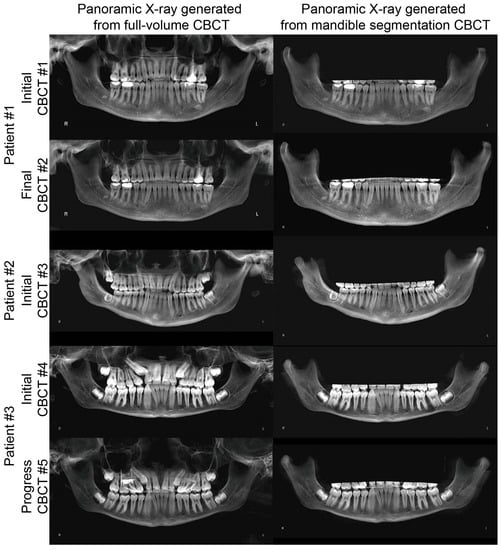

3. Results